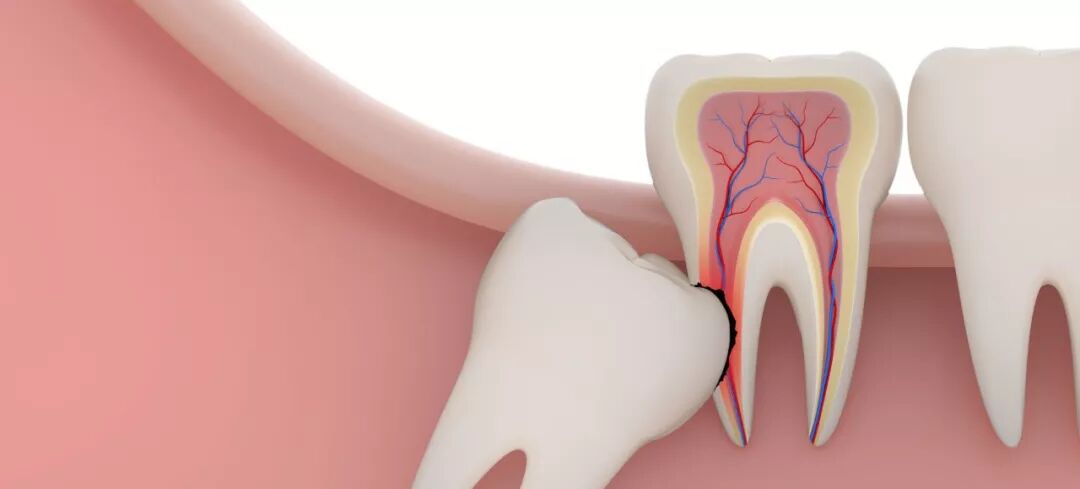

丨智齿引起其他牙齿问题,例如邻牙龋坏等

智齿不仅自己不乖,还要带坏旁边的好牙齿!阻生智齿通常萌出空间不足。

一般智齿如果倒在第二磨牙上,鸠占鹊巢,会先导致牙根吸收、吸收到一定程度才会疼痛,此时去看诊,基本是要么得做根管治疗,要么这颗牙齿就阵亡了。